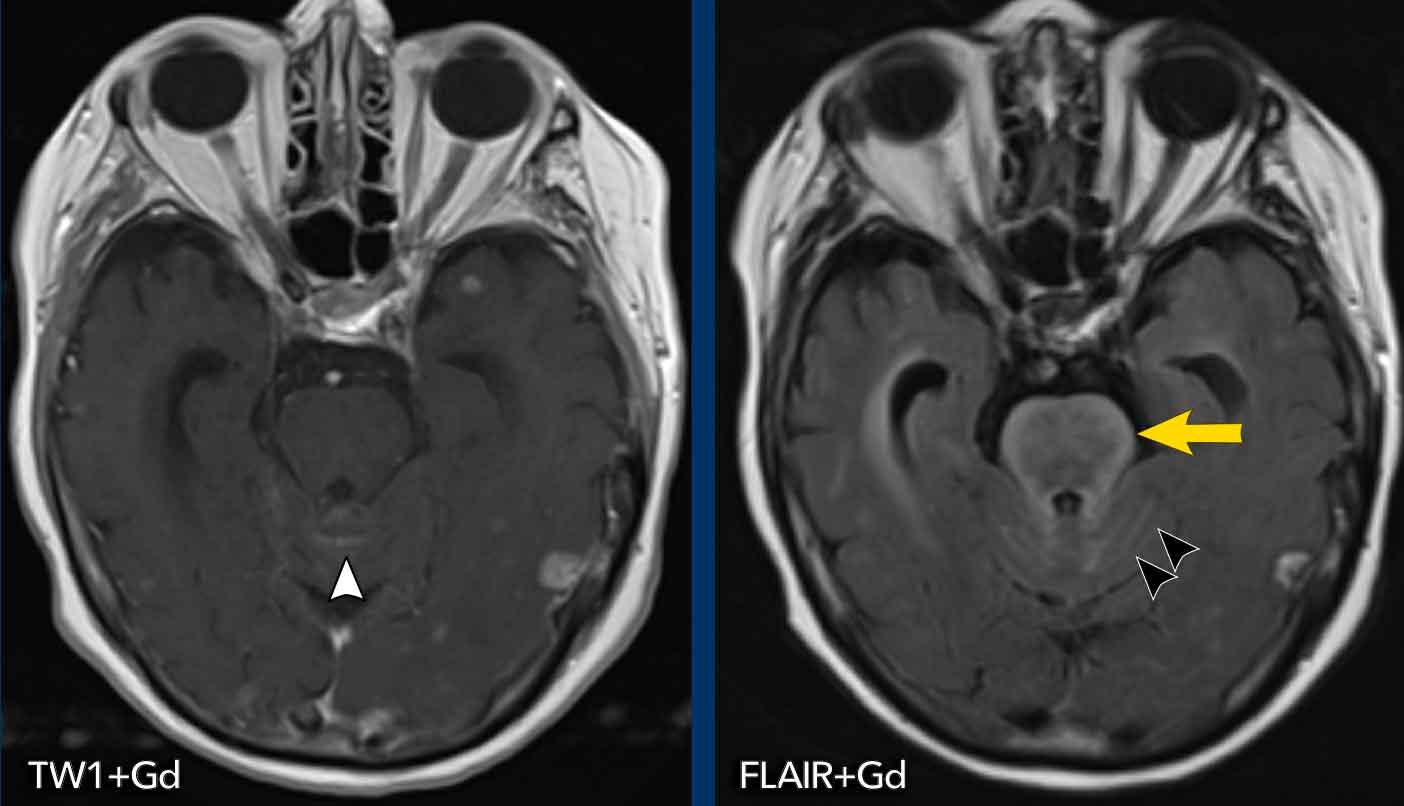

Khả năng phát hiện các ổ tổn thương và ngấm thuốc màng não mềm có thể được cải thiện bằng cách sử dụng chuỗi xung FLAIR có tiêm thuốc tương phản từ.

Tương tự như trong viêm màng não, cũng cần quan sát khoang dưới nhện trên FLAIR không tiêm thuốc.

Thông thường trên các hình ảnh này, dịch não tủy bị xóa tín hiệu, nhưng trong trường hợp bệnh lý, dịch não tủy sẽ xuất hiện tăng tín hiệu hơn.

Các ví dụ này cho thấy ưu điểm của FLAIR+Gd so với T1W+Gd ở bệnh nhân ung thư phổi có di căn não và viêm màng não do ung thư.

Hình ảnh

Hình ảnh FLAIR thể hiện rõ hơn ngấm thuốc màng não mềm xung quanh cầu não (mũi tên vàng) và trong các nếp gấp tiểu não (đầu mũi tên đen).